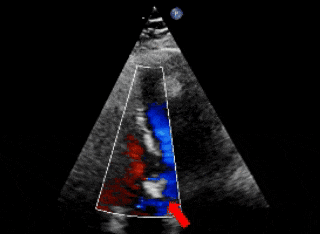

术前超声

超声下可见左盘面贴靠主动脉侧

超声下可见双盘面骑跨

封堵器形态良好,基本无残余分流